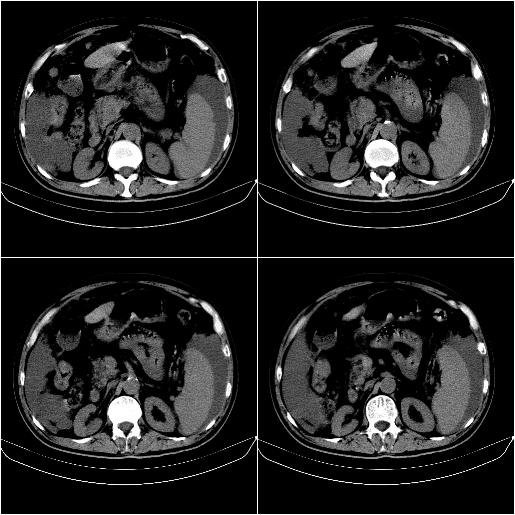

标题: CT21651:M,67Y,肝癌9月,介入术后3月。

m,67y,肝癌9月,介入术后3月。现腹胀、纳差、腹泻。

脾脏转移。。。

1)肝癌介入治疗术后碘油沉积不良。2)门静脉瘤栓形成,腹膜广泛性转移。3)肝硬化,脾大,腹水。4)慢性胆囊炎。